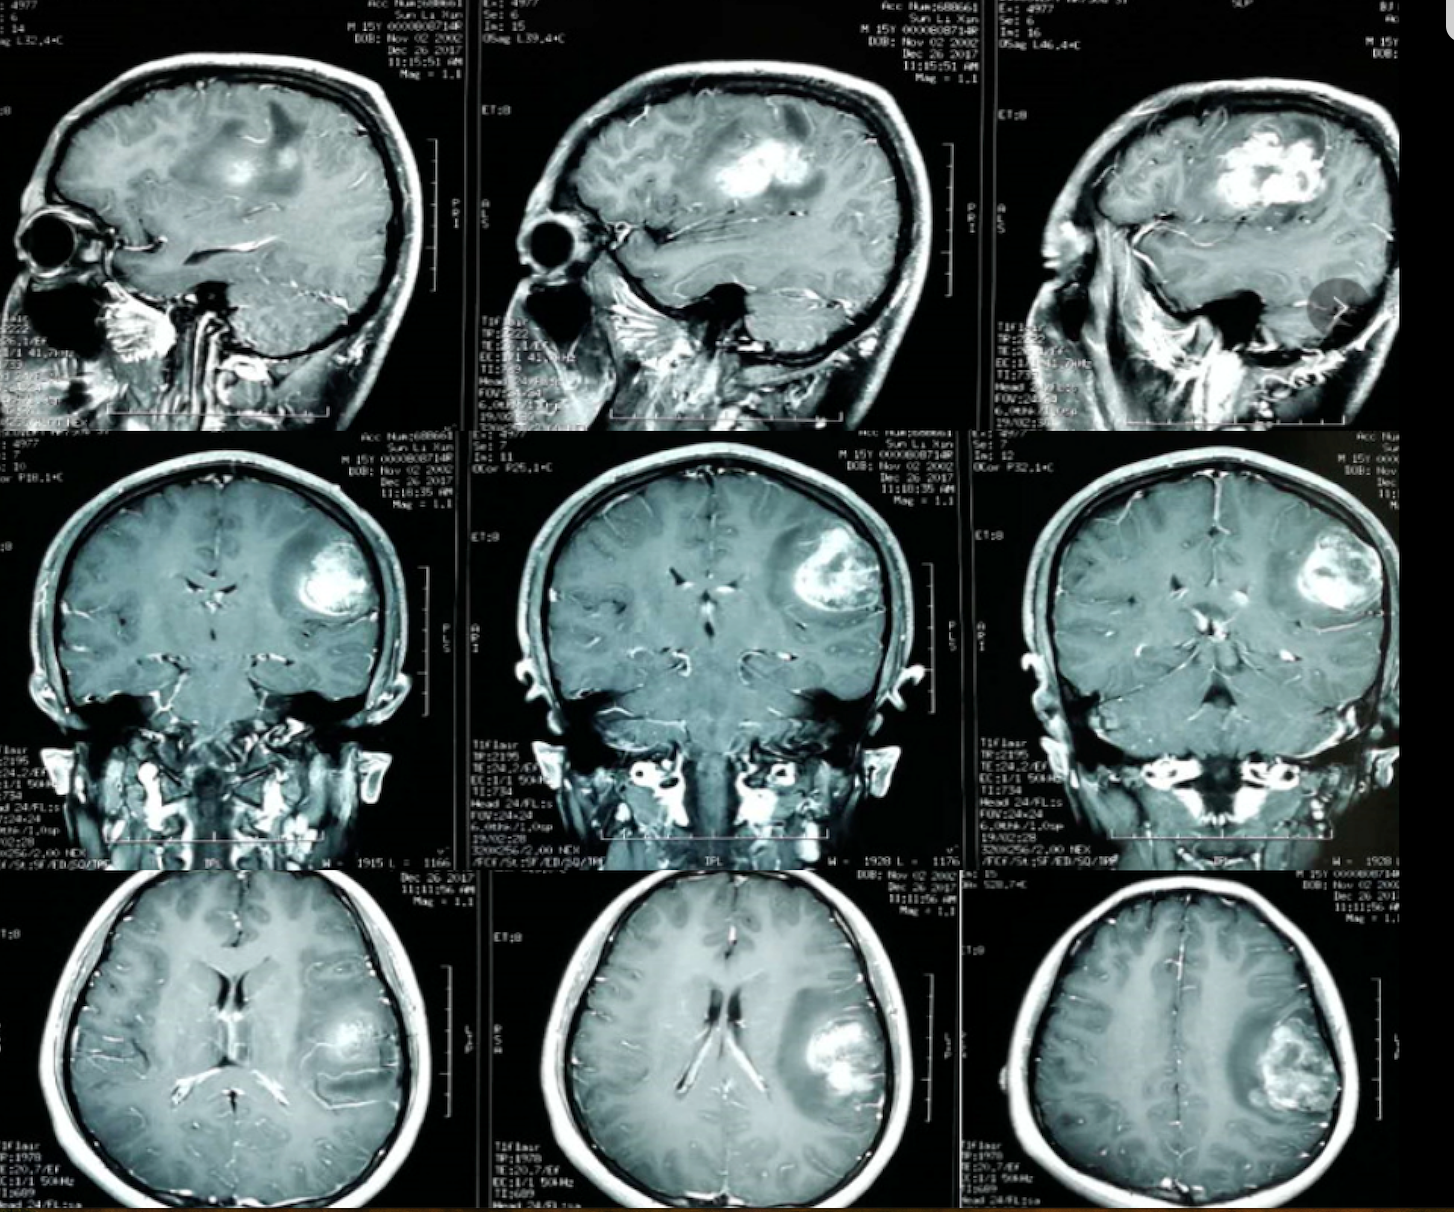

多模态影像融合助力精准切除功能区胶质瘤

多模态影像融合及术中导航技术精准切除功能区胶质瘤